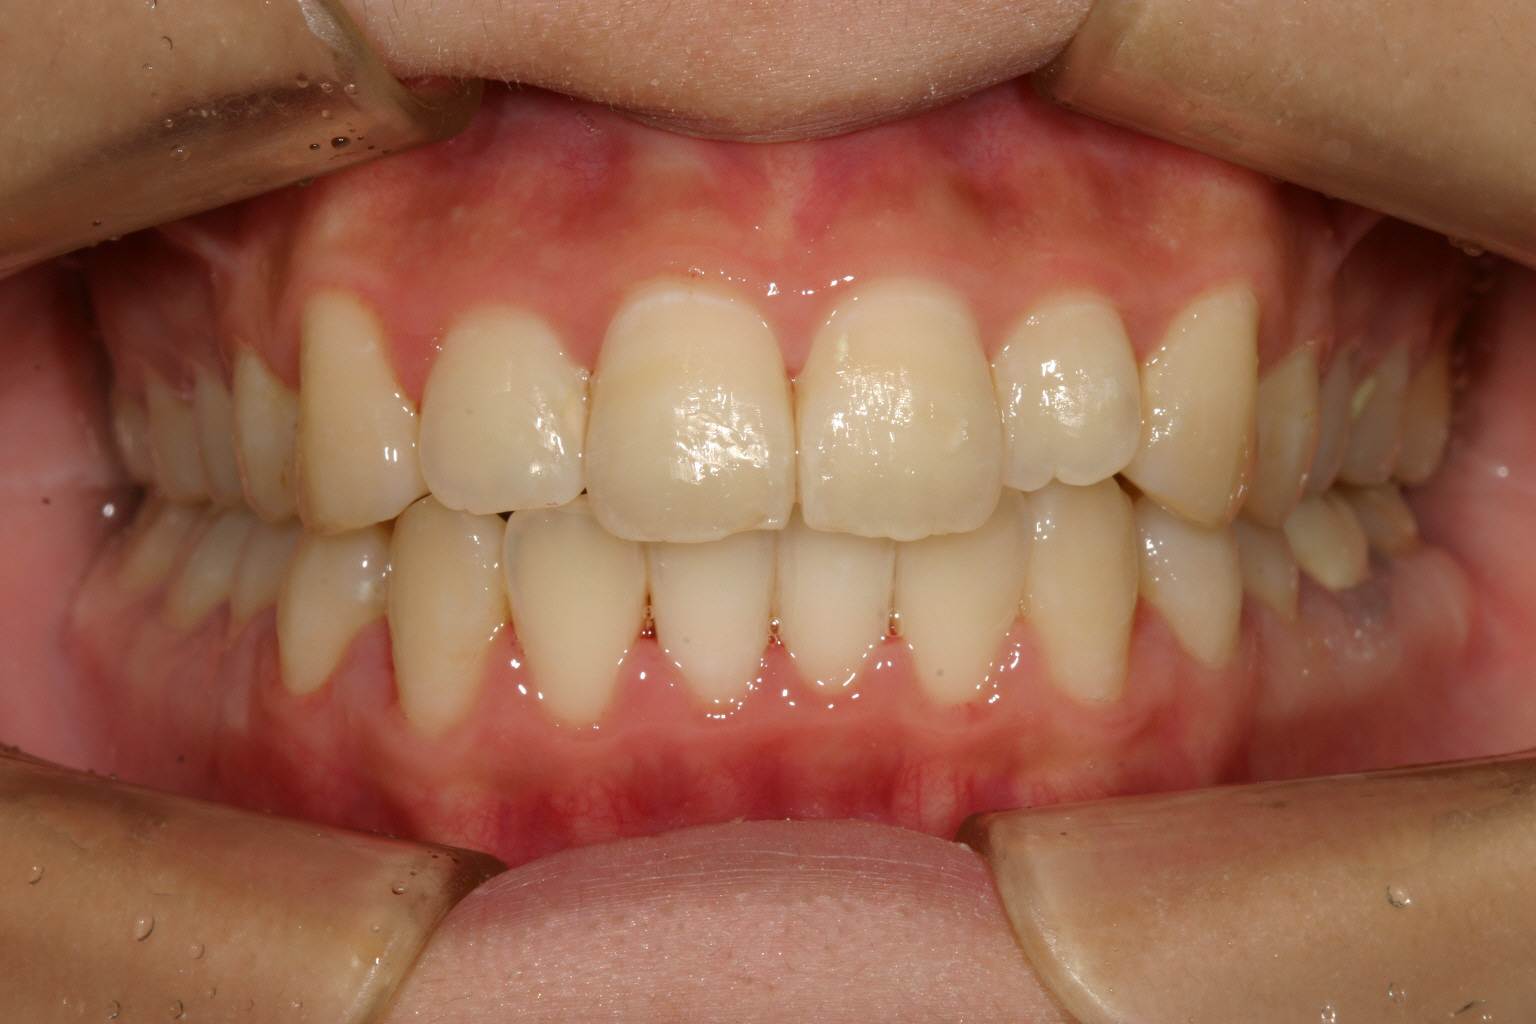

ご覧ください! 綺麗にでっぱ改善しました。

今回のケースは上下顎前突の為インビザラインによるアーチフォームの拡大とIPR(歯と歯の間を少し削る事)により抜歯せずともここまで改善しました。